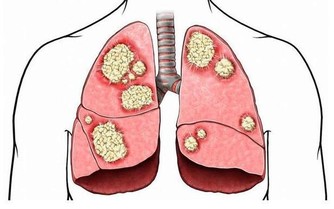

3. 儘早戒菸,遠離多個癌症

醫生指出,菸酒是打開癌症大門的推手,每天吸煙20支以上的人,患癌風險比不吸煙者高出若干倍,且女性比男性患癌風險更大。

吸煙不僅和肺癌有關,它還會讓人更易得胃癌、結直腸癌、宮頸癌、乳腺癌等癌症,都是鐵證如山。

記住:及時戒菸很重要,別等出事了再來後悔!